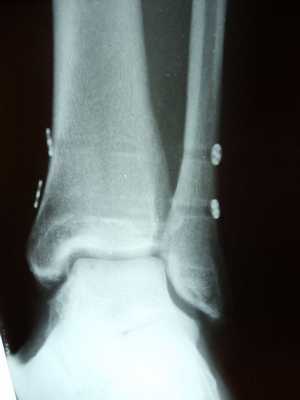

В подавляющем большинстве случаев возникает необходимость в оперативном лечении. Классическая методика заключается в фиксации синдесмоза позиционными винтами. Для этой цели подойдут 3,5 или 4,5 мм синдесмозные винты проведённые через 3 или 4 кортикальных слоя на 2-5 см выше дистального плато большеберцовой кости.

Установку винтов лучше производить в положении тыльного сгибания стопы, что позволяет предотвратить «перезатягивание». В послеоперационном периоде потребуется 6-12 недель ходьбы с костылями без нагрузки на оперированную конечность, с последующим удалением винтов.

Собственно фиксация дистального межберцового синдесмоза возможна как при помощи винтов, так и при помощи пуговчатых фиксаторов. Фиксацию лучше выполнять через небольшой кусок 1\3 трубчатой пластины, чтобы распределить нагрузку на большую площадь. В противном случае существует риск последующего перелома малоберовой кости по винту, так как он будет концентрировать на себе всю нагрузку.

В случае если фиксация производится винтом или винтами, лучше использовать трёхкортикальный метод, так как он обеспечивает менее жёсткую фиксацию, и позволяет малоберцовой кости её нормальные физиологические движения в вырезке. Четырёхкортикальные винты блокируют малоберцовую кость более жёстко. И препятствуют тыльному сгибанию стопы. После начала нагрузки четырёхкортикальные винты часто ломаютя, по той же причине.